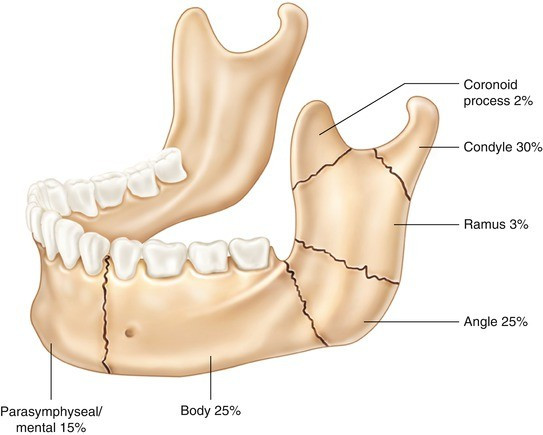

Fraktur Mandibula

Fraktur mandibula adalah salah satu fraktur pada daerah wajah yang cukup sering terjadi